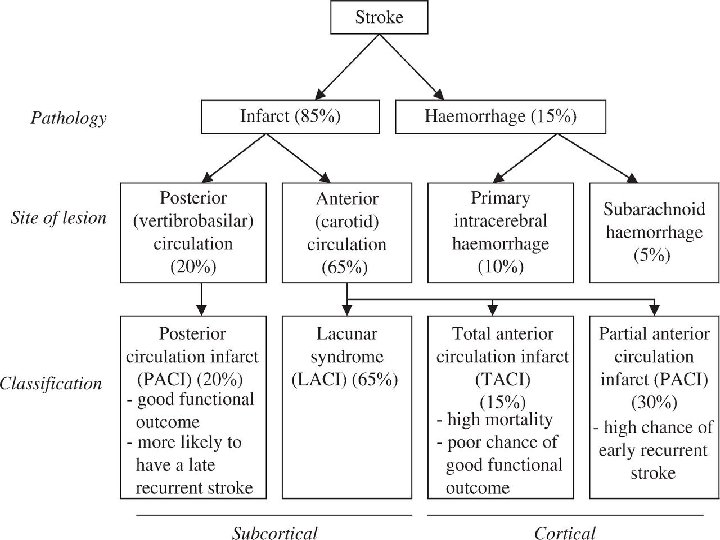

Stroke Ischaemic stroke/infarction (80%) Ø Thrombotic Ø Cardio-embolic Ø Large artery stenosis Ø Small vessel disease Ø Hypoperfusion Haemorrhagic stroke (17%) Ø Intracerebral hemorrhage (12%) Ø Subarachnoid hemorrhage (5%) Other (3%), e. g. arterial dissection, venous sinus thrombosis, vasculitis

Types of Stroke Depending upon the blood supply of affected area of brain, stroke can be of following types: § ANTERIOR CIRCULATION STROKE: Carotid system § POSTERIOR CIRCULATION STROKE: Vertebrobasilar system